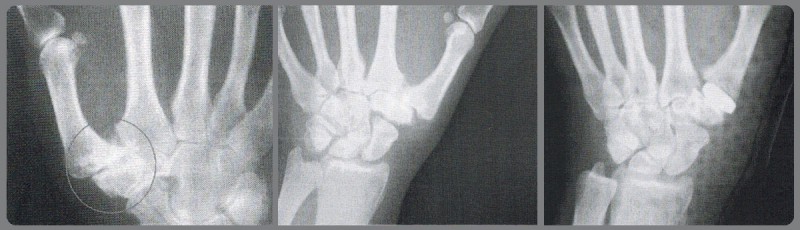

La diagnosi è clinica, mediante la visita di uno specialista ortopedico o meglio di un chirurgo della mano. Un esame radiografico ed eventualmente una TAC consentono di valutare la gravità del quadro artrosico e indirizzano verso il tipo di terapia.

In questi casi l’esame radiografico specifico per indagare questa articolazione ed eventualmente una TAC consentono di valutare il grado di artrosi (danno articolare) delle ossa alla base del pollice, indirizzando il chirurgo verso il tipo di intervento da eseguire.